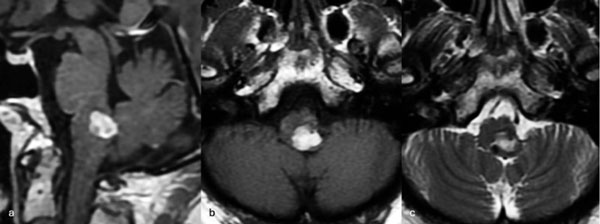

Caso 4: cavernoma bulbar

Una mujer de 53 años, con antecedentes de dos sangrados previos, consultó por un cuadro de perfil agudo caracterizado por tetraparesia asociada a compromiso de pares craneales bajos, que requirió instalación de una traqueostomía. La RM de encéfalo evidenció una malformación cavernomatosa en relación al bulbo izquierdo (Figura 9). Un mes después del último sangrado, la paciente fue sometida a una exéresis de la lesión mediante un abordaje suboccipital de línea media, vía intertonsilar (Figura 10), logrando una exéresis completa (Figura 11). Luego de la cirugía la paciente evolucionó con mejoría parcial de sus síntomas de ingreso, sin agregar nuevos déficits neurológicos.

Figura 9. RM preoperatoria de encéfalo. Se evidencia una lesión única intraaxial bulbotrigonal izquierda, que contacta la mitad inferior del piso del cuarto ventrículo, hiperintensa en T1 y T2, con vacíos de flujo que impresionan provenir de una malformación del desarrollo venoso, lo que sugiere una malformación cavernomatosa. A) Imagen en corte sagital ponderada en T1 posterior a la administración de gadolinio. B y C) Imágenes en corte axial ponderadas en T1 y T2, respectivamente.

Figura 11. RM postquirúrgica de encéfalo. Se evidencia una exéresis completa, sin daño del parénquima adyacente. A) Imagen en corte sagital ponderada en T1 posterior a la administración de gadolinio. B y C) Imágenes en corte axial ponderadas en T1 posterior a la administración de gadolinio y T2, respectivamente.